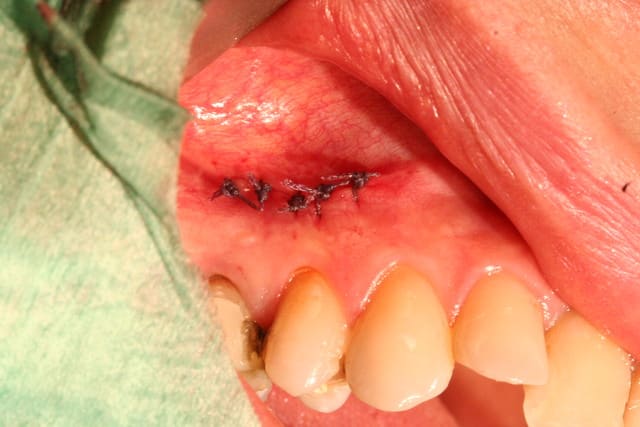

Je viens de faire l'extraction ce matin.

Je rage de ne pas l'avoir fait encore plus tôt car c'est bien ce que je craignais, toute la table externe a été bouffée par l'infection...

J'ai cureté très soigneusement et irrigué puis mis matériaux de comblement pour limiter l'effondrement en vestibulaire.

juste pour le fun.

résection apicale faites chez un endo exclusif au Luxembourg (attention les mauvaises langues, c'est pas l'Amibe!) il y a 3 trois ans.

je vous laisse juger...